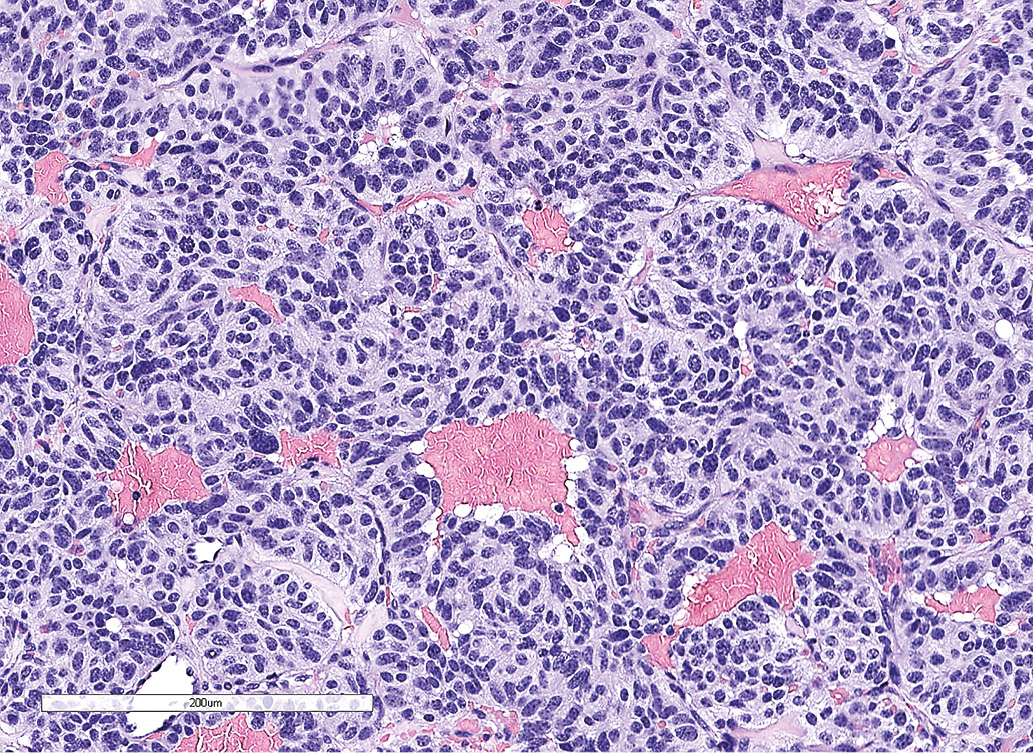

По данным патоморфологического исследования, выявлены фрагменты опухоли из железистоподобных структур, клетки которых обладали признаками нейроэндокринной дифференцировки (рис. 2.1). По данным иммуногистохимического исследования, в клетках опухоли обнаружена экспрессия TTF-1, хромогранина А, низкомолекулярного цитокератина (клон САМ 5.2), что свидетельствовало о наличии метастаза нейроэндокринной опухоли легкого. Экспрессия гормонов гипофиза (АКТГ, СТГ, ПРЛ, ТТГ, ЛГ, ФСГ) отсутствует. Индекс метки Ki-67 составил 12,2% (рис 2.2, 2.3).

Рисунок 2.1. Окраска гематоксилином и эозином. Железисто-подобные структуры и клетки опухоли с признаками нейроэндокринной дифференцировки.